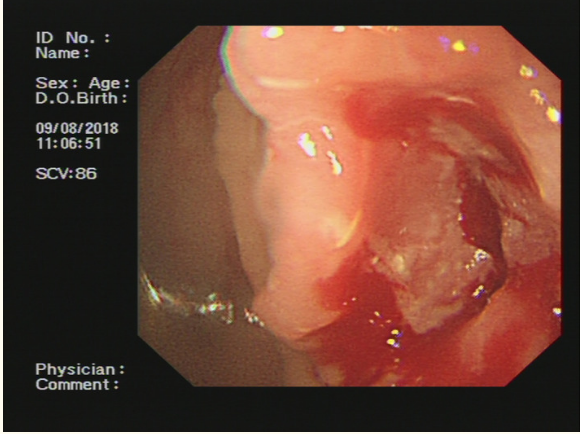

一名54岁的的男性患者,体重指数16.5,近两个月出现食欲不振以及体重降低,抽血检查发现癌胚抗原CEA7.77ng/mL,CA19-9水平为357.3U/ml,腹部CT提示结肠肝区肿瘤,侵袭肝脏VI段和VII段,胆囊,十二指肠,如图1所示;结肠镜检查发现结肠肝曲肿瘤占位,如图2所示。取活组织病理提示低分化管状腺癌。

图2 结肠镜检查发现结肠肝曲肿瘤占位